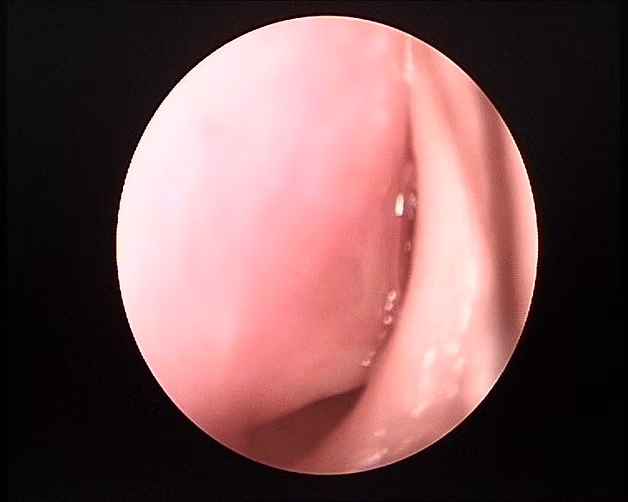

Antes de la cirugía - Septoplastia

Se observa el tabique nasal y columela desviada hacia la izquierda provocando dificultad para respirar y ronquido nocturno.